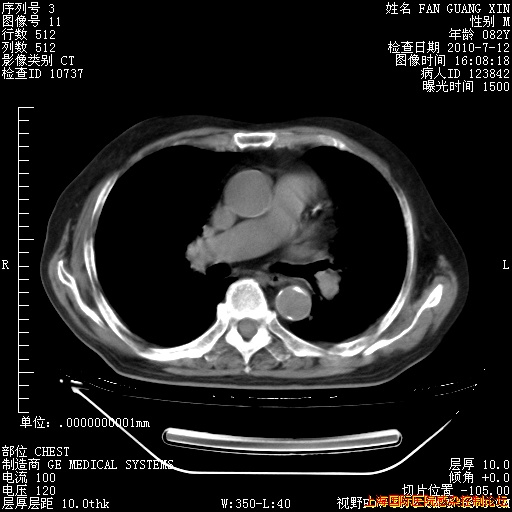

今天复查CT

今天CT

整整相隔30天的肺部CT好像有所好转啊。甲强龙减量第3天,需要观察体温。

海管,自昨日你和我通完话后,不知您岳父消化道症状有无缓解?体温怎样?阅读7.12日胸部ct,个人认为目前激素治疗是有效的,甲强龙减量是适宜的。因在抗痨治疗,需密切观察肝功、肾功能和血常规。不过,老年、长期住院和大量使用激素,很担心菌群失调发生